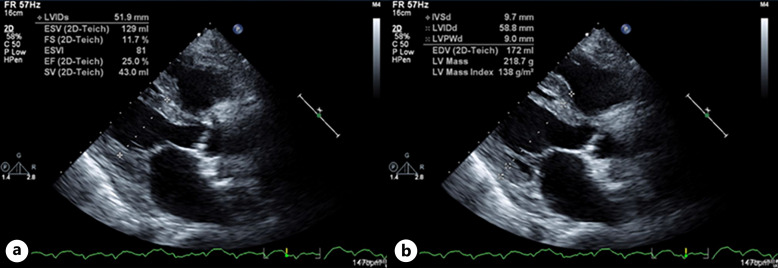

Case presentation: We encountered a case of advanced renal cancer in which immune checkpoint inhibitor-associated myocarditis was confirmed on autopsy. A 78-year-old man was diagnosed with a left renal tumor secondary to hematuria. A tumor biopsy was performed, and the tumor was diagnosed as cT4N0M1 clear cell renal carcinoma, which was classified as poor risk by the International mRCC Database Consortium. Combination therapy with pembrolizumab and axitinib was initiated. One month later, the patient developed anorexia, dizziness, and fatigue, which were judged to be adverse events due to systemic therapy, and the patient was admitted to the hospital urgently. After admission, the patient experienced a sudden drop in blood pressure and loss of consciousness and was referred to a cardiologist for treatment. Blood tests showed elevated brain-type natriuretic peptide levels, but echocardiography showed good cardiac function. However, soon thereafter, the patient developed tachycardia, and echocardiography revealed a significant decline in systolic function, leading to the diagnosis of immune checkpoint inhibitor-associated myocarditis. Despite intensive care in the cardiac high-care unit and steroid administration, the patient died. An autopsy revealed necrotic changes in the myocardium, loss of myocardial cells, and severe lymphocyte infiltration, leading to a diagnosis of inhibitor-associated myocarditis.